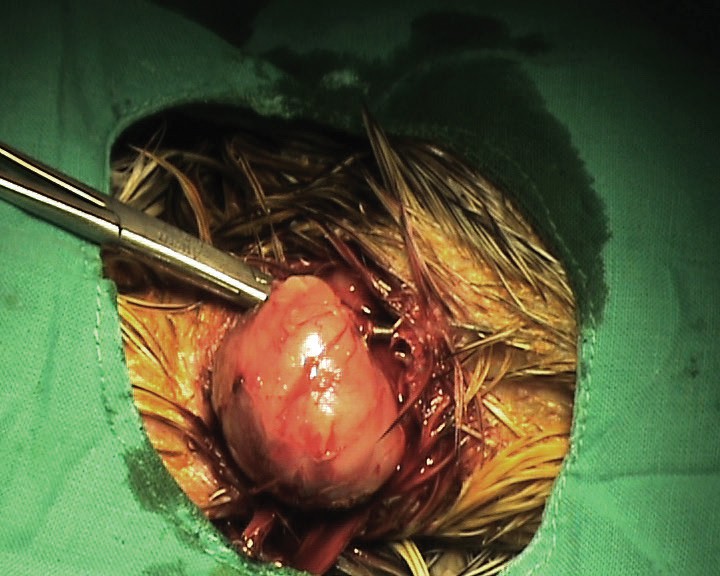

En la exploración física se observó una masa redonda en la cara ventral del cuello (Fig. 3), fluctuante, indolora, de aproximadamente 2 cm de diámetro, localizada en el tejido subcutáneo (Fig. 4), sin afectar ni adherirse a la piel que clínicamente se diagnosticó como un lipoma. Después de la extirpación quirúrgica (Fig. 5), se envió una muestra para histopatología e inmunohistoquímica.

<p>Aspecto de la masa en el momento de la extracción quirúrgica.</p>

Aspecto de la masa en el momento de la extracción quirúrgica.